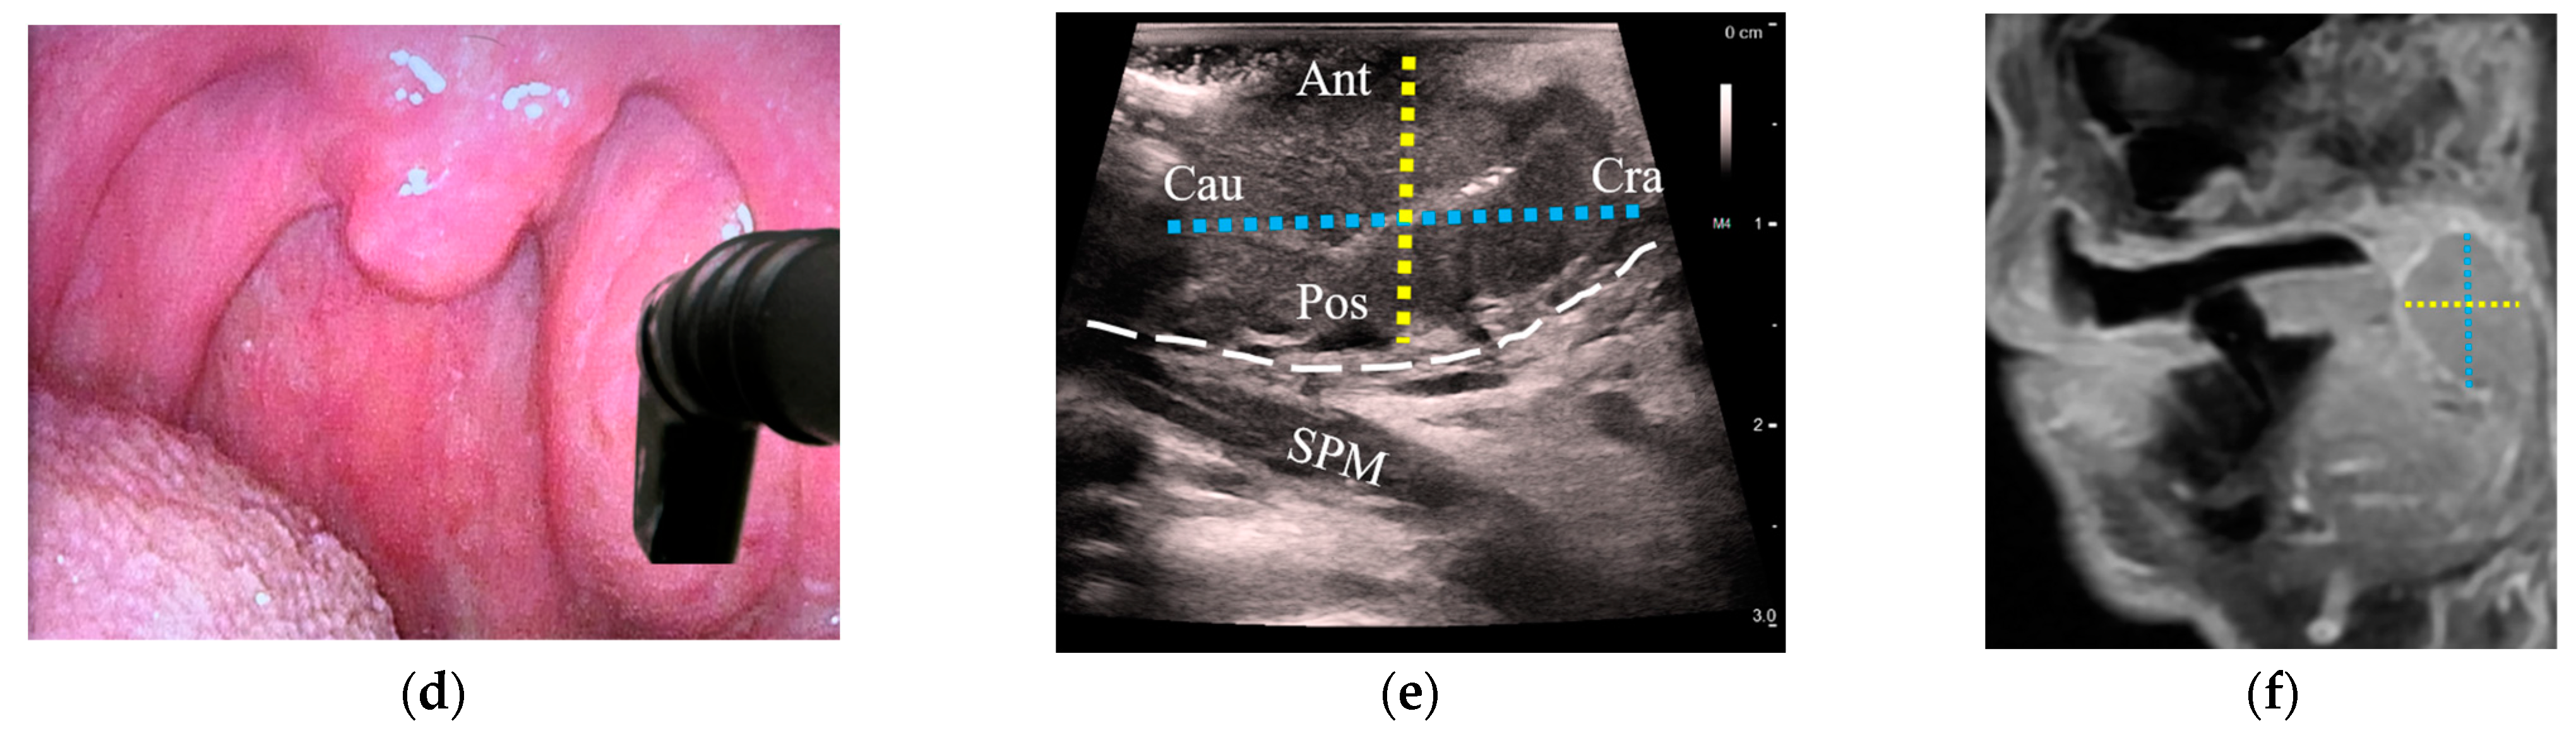

3.3. Detection of OPCs Compared between US and MRI

3.4. Comparison of T-Staging between US and MRI

3.4.1. Correlation of the Greatest Tumor Size

3.4.2. Agreement of Categorical T-Stage